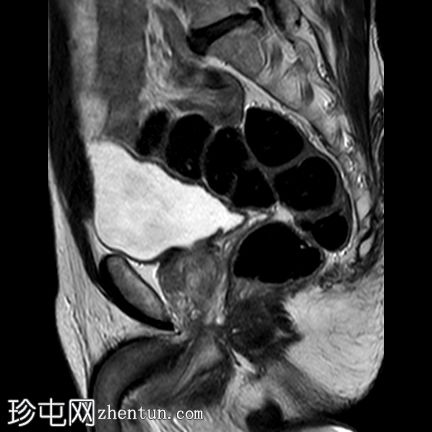

矢状位

T2加权像

右侧前列腺前中带可见一边界不清的18 x 10 mm扁豆状病灶,T2加权像呈低信号,扩散受限(DWI高信号,ADC低信号),与周围实质相比早期强化,病灶位于前移行区与纤维肌性间质交界处。影像学表现符合PI-RADS 5级病灶。

未见前列腺外侵犯、盆腔淋巴结肿大或疑似骨病变。

T2加权像显示骶骨翼骨髓高信号,T2/STIR序列抑制,提示脂肪骨髓沉积。